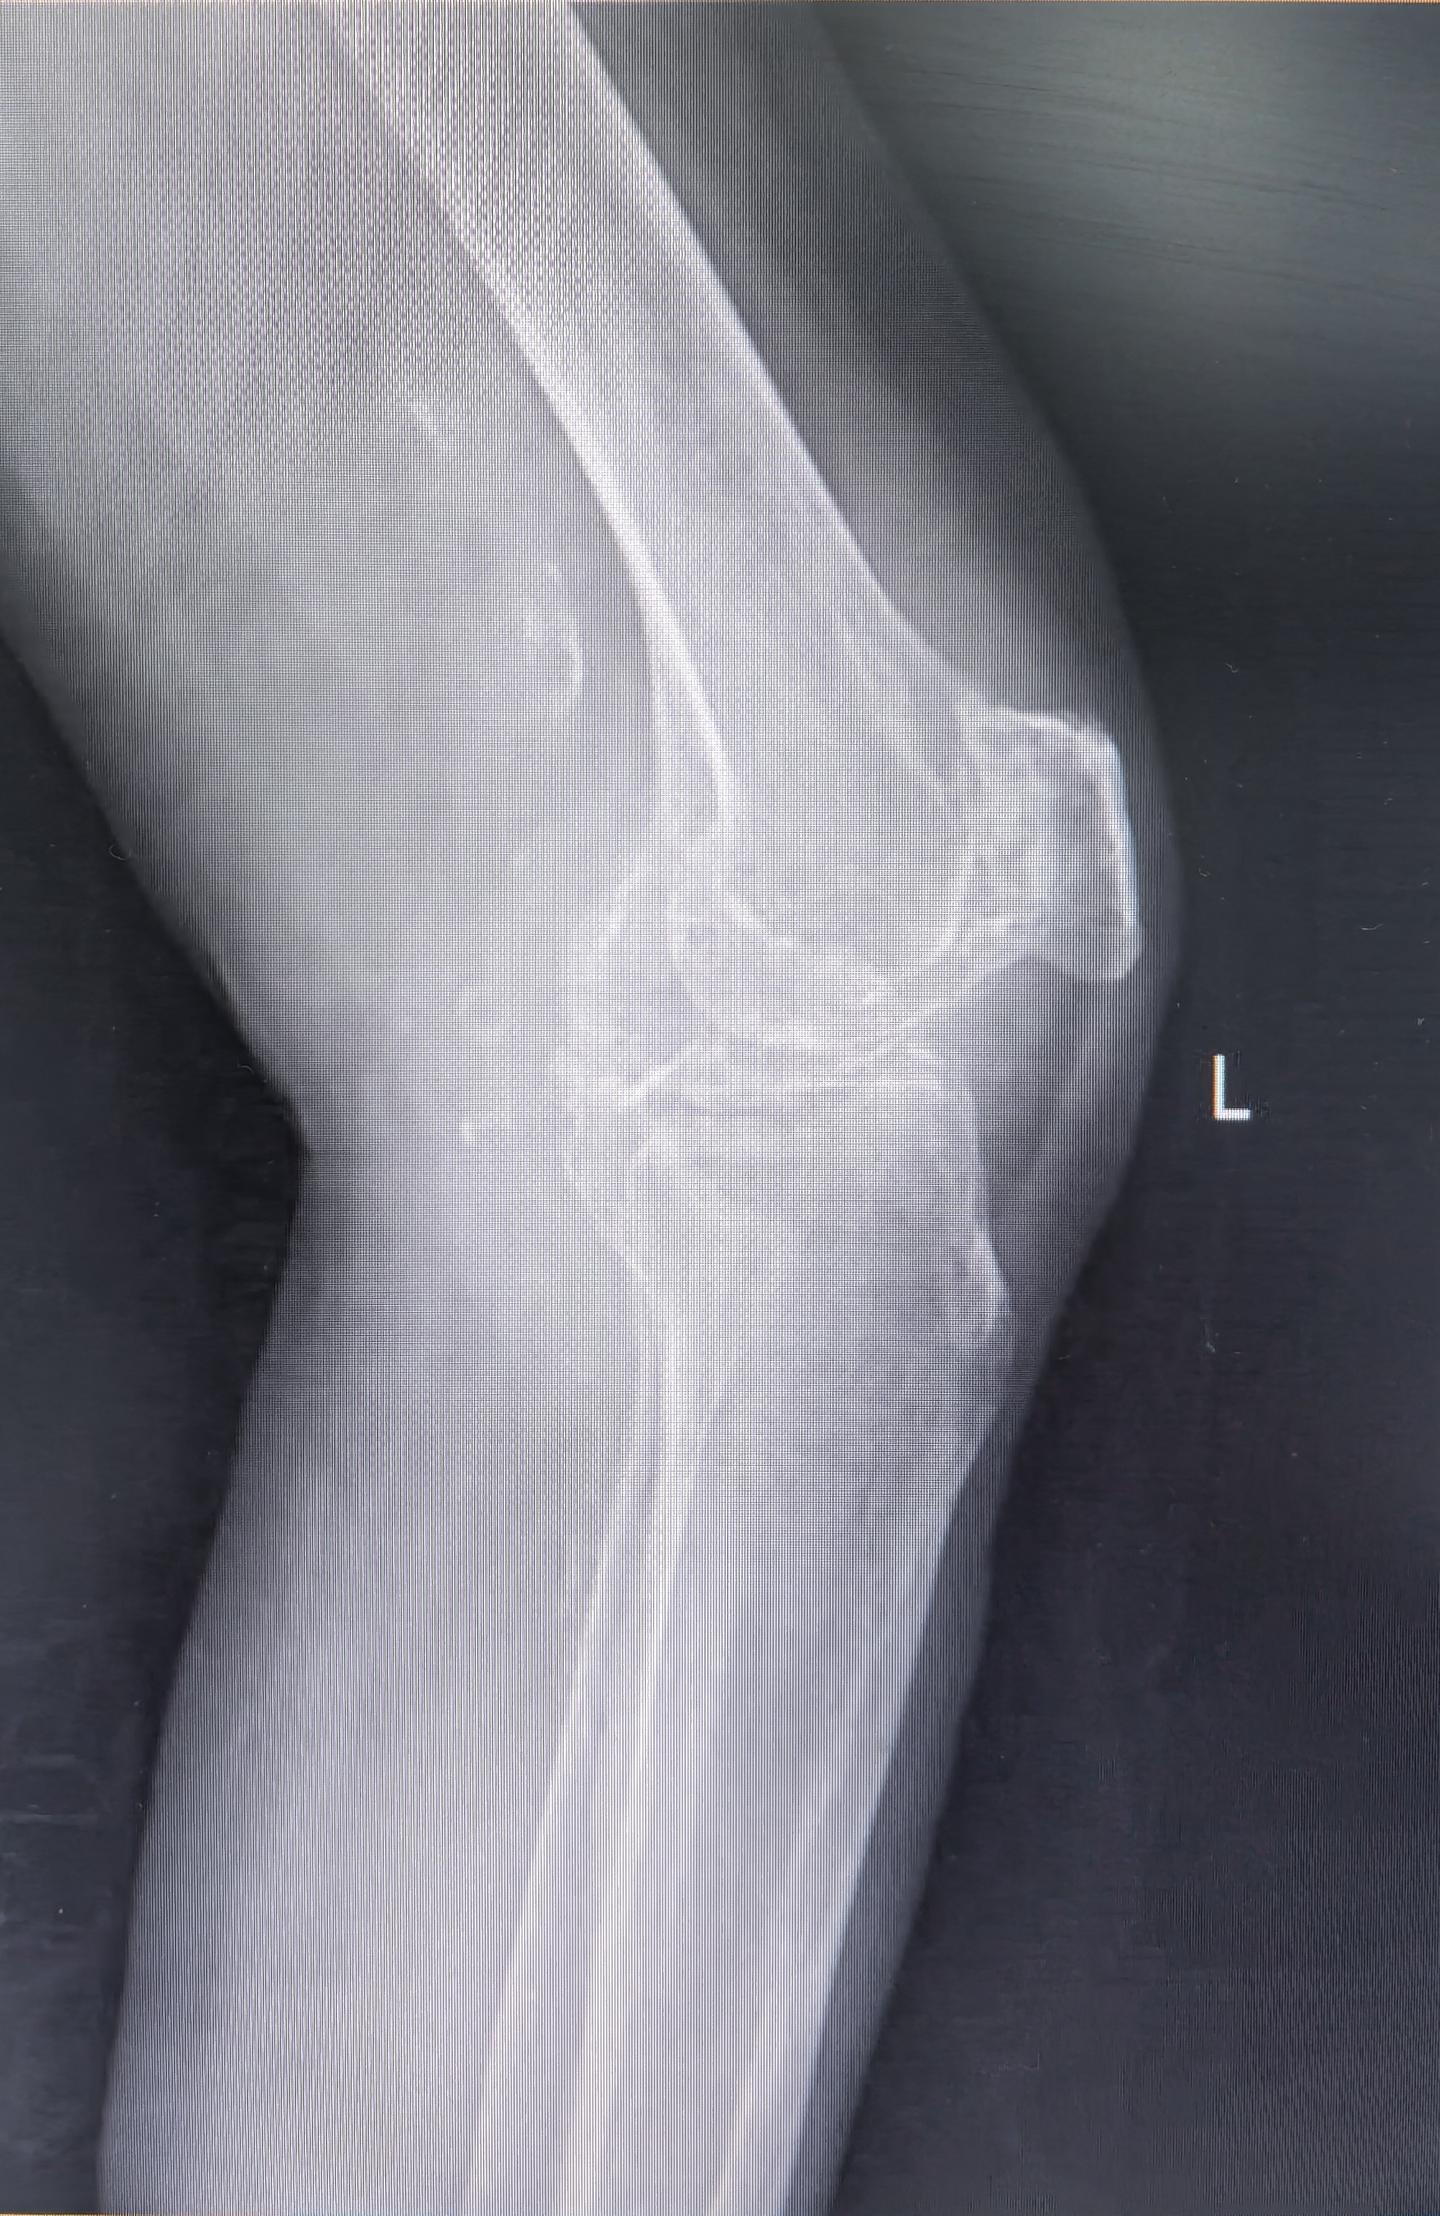

膝关节置换TKA.受罪多年的85岁老爷子,终于下定了决心。其实骨性关节炎到了这种地步,伸不直蜷不住,走路都困难,真是早做早受益。